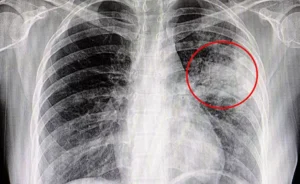

しかし、久しぶりにスイッチを入れてみると「何だかカビ臭い」このまま使い続けても大丈夫なのだろうか?と心配になる方も多いのではないでしょうか?エアコンのカビを放置することで夏型過敏性肺炎の原因になる場合もあると医師が解説されています。

実際に当店でも、エアコンクリーニングのご依頼を頂きお伺いすると、エアコンのカビを放置した結果、部屋中にカビの胞子が飛び散り、部屋のいたるとことにもカビが発生し、肺炎をはじめとするシックハウス症候群を発症されたという方も少なくありません。

実際に梅雨時期になると、カビが原因と考えられる肺炎に悩まされ、カビ取りのご相談をいただくというケースも出てきます。

エアコンのカビを放置して使い続けると肺炎やシックハウス症候群など健康に被害が及ぶ可能性があります。